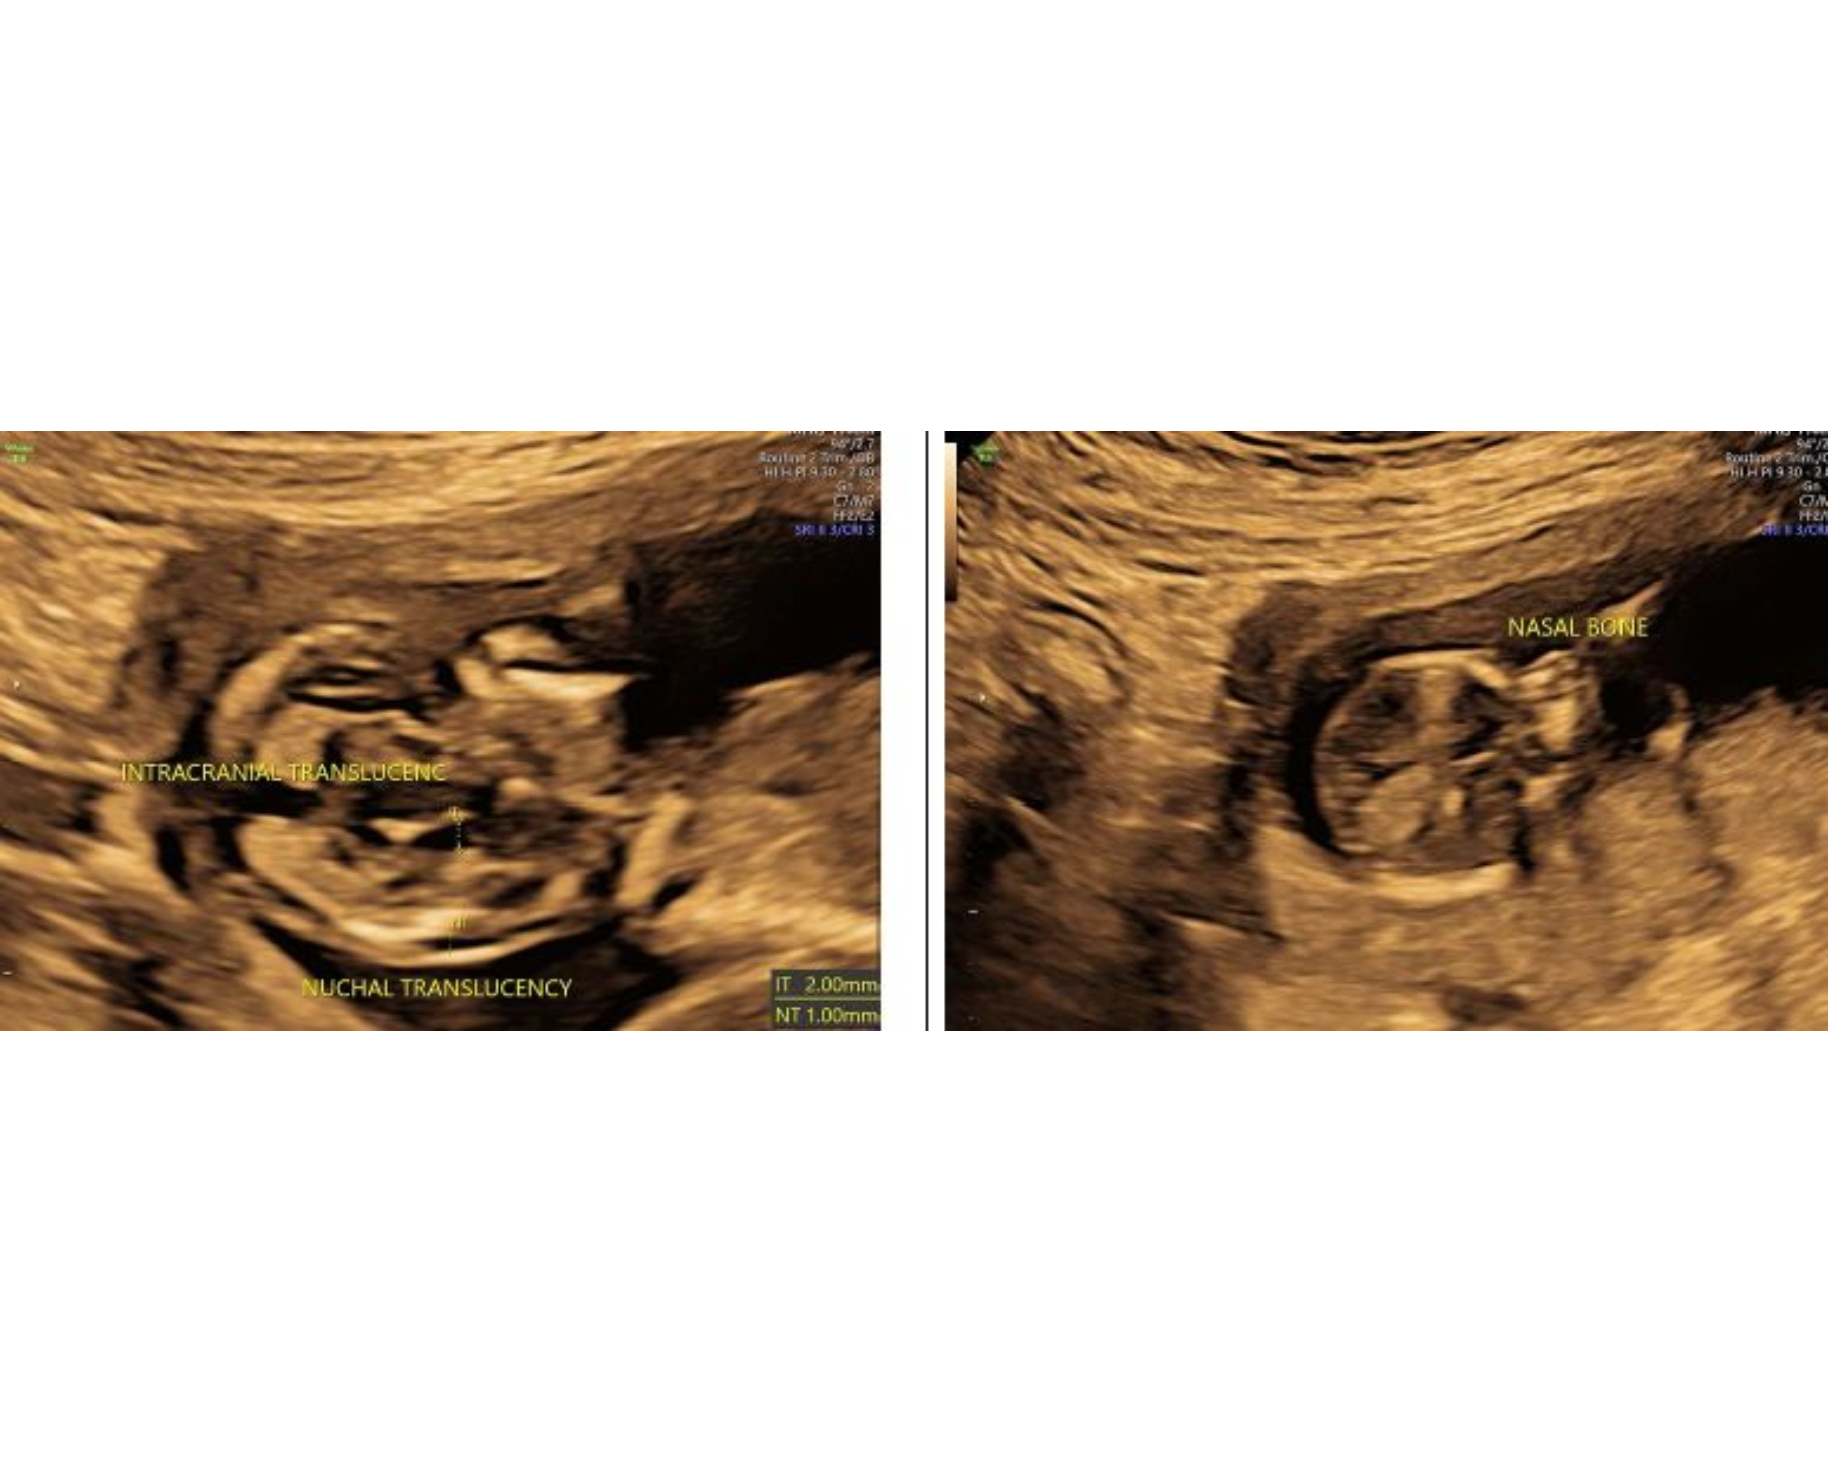

NTNB ultrasound available in rohini delhi ntnb ult...